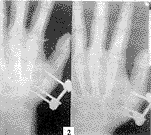

224-t2.gif (4614 bytes)

图2 术后第6周

骨折愈合时间为4~8周(图2),平均5.2周。无骨折再移位、骨不连。骨折愈合后经6~12个月随访,掌指关节或指间关节活动功能均基本恢复正常,掌指关节活动度为20°(伸)90°(屈),指间关节活动度为近侧屈曲85°,远侧屈曲70°~80°。有2例针眼感染经利凡诺尔换药后控制。